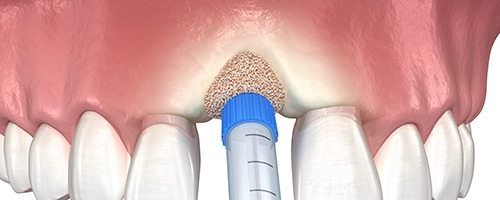

Операция проводится с помощью подсадки костного материала и закрепления его с помощью мембраны, она является одним из наиболее эффективных методов костной пластики. Используется для восстановления объема или увеличения и высоты костной ткани при истончении кости в области альвеолярного гребня на верхней или нижней челюсти. Операция проводится с применением местной анестезии и может занимать до полутора часов. Пациенты, которые страдают от вертикальной резорбции после потери зубов, нуждаются в наращивании костной ткани в пострадавшей области для установки имплантов и последующего протезирования.

Операция проводится с помощью подсадки костного материала и закрепления его с помощью мембраны, она является одним из наиболее эффективных методов костной пластики. Используется для восстановления объема или увеличения и высоты костной ткани при истончении кости в области альвеолярного гребня на верхней или нижней челюсти. Операция проводится с применением местной анестезии и может занимать до полутора часов. Пациенты, которые страдают от вертикальной резорбции после потери зубов, нуждаются в наращивании костной ткани в пострадавшей области для установки имплантов и последующего протезирования.

Проводится и для верхней, и для нижней челюсти. Суть метода в ведении специального костного материала, который провоцирует регенерацию собственной кости. Их (материалов) существует несколько видов: аутогенные, аллогенные, ксеногенные — и доктор подбирает, подходящий индивидуально именно вашему организму.

Проводится и для верхней, и для нижней челюсти. Суть метода в ведении специального костного материала, который провоцирует регенерацию собственной кости. Их (материалов) существует несколько видов: аутогенные, аллогенные, ксеногенные — и доктор подбирает, подходящий индивидуально именно вашему организму.